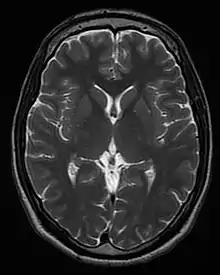

| T2 weighted | T2 | Measuring spin–spin relaxation by using long TR and TE times |

Standard foundation and comparison for other sequences |

Each tissue returns to its equilibrium state after excitation by the independent relaxation processes of T1 (spin-lattice; that is, magnetization in the same direction as the static magnetic field) and T2 (spin-spin; transverse to the static magnetic field). To create a T1-weighted image, magnetization is allowed to recover before measuring the MR signal by changing the repetition time (TR). This image weighting is useful for assessing the cerebral cortex, identifying fatty tissue, characterizing focal liver lesions, and in general, obtaining morphological information, as well as for post-contrast imaging. To create a T2-weighted image, magnetization is allowed to decay before measuring the MR signal by changing the echo time (TE). This image weighting is useful for detecting edema and inflammation, revealing white matter lesions, and assessing zonal anatomy in the prostate and uterus.